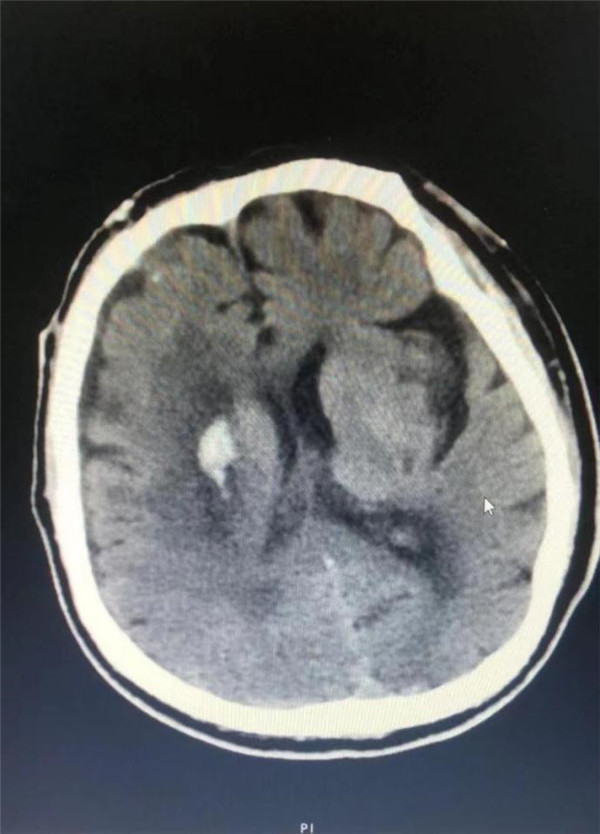

术后CT 血肿基本清除

该手术是采用了国内首台脑出血手术机器人——睿米RM50来导航。有了这位“智能助手”的帮忙,大大缩短了手术时间,手术过程非常顺利,术后血肿大部分引出,目前,患者体征平稳,恢复良好。该术式达到了微创伤、精准定位、安全高效地对出血性中风病人的脑内血肿定位,穿刺抽吸血肿的治疗目的,同时能一定程度上改善保守治疗时脑内血肿长期压迫所致的神经损伤症状。